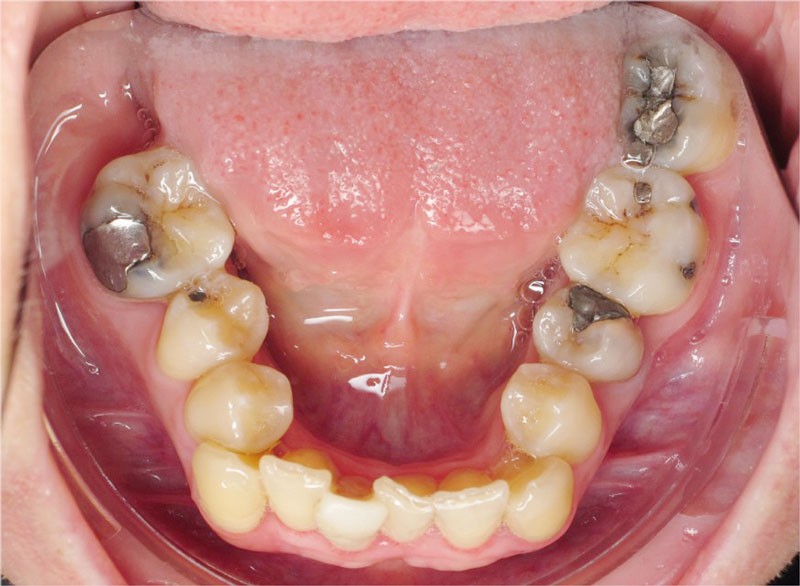

Nous lui avons donc proposé un traitement d’alignement avec maintien des 14 et 24 en position de 13 et 23 et optimisation du torque pour favoriser un développement des arcades et chercher à améliorer le sourire et le soutien labial.

Un appareillage Damon métal a été mis en place, réalisé à partir d’un set up numérique Insignia pour obtenir un contrôle précis des torques et de la forme d’arcade et réduire le temps de finition grâce à un collage indirect très précis.

De larges surélévations postérieures étalées ont été mises en place et la patiente a porté des élastiques précoces suivant les principes de la technique Damon. Les 14 et 24 rempliront le rôle des 13 et 23.

L’objectif, en utilisant la technique Insignia est de réduire le temps de traitement de 28 à 18 mois avec 12 rendez-vous (fig. 5 à 14).